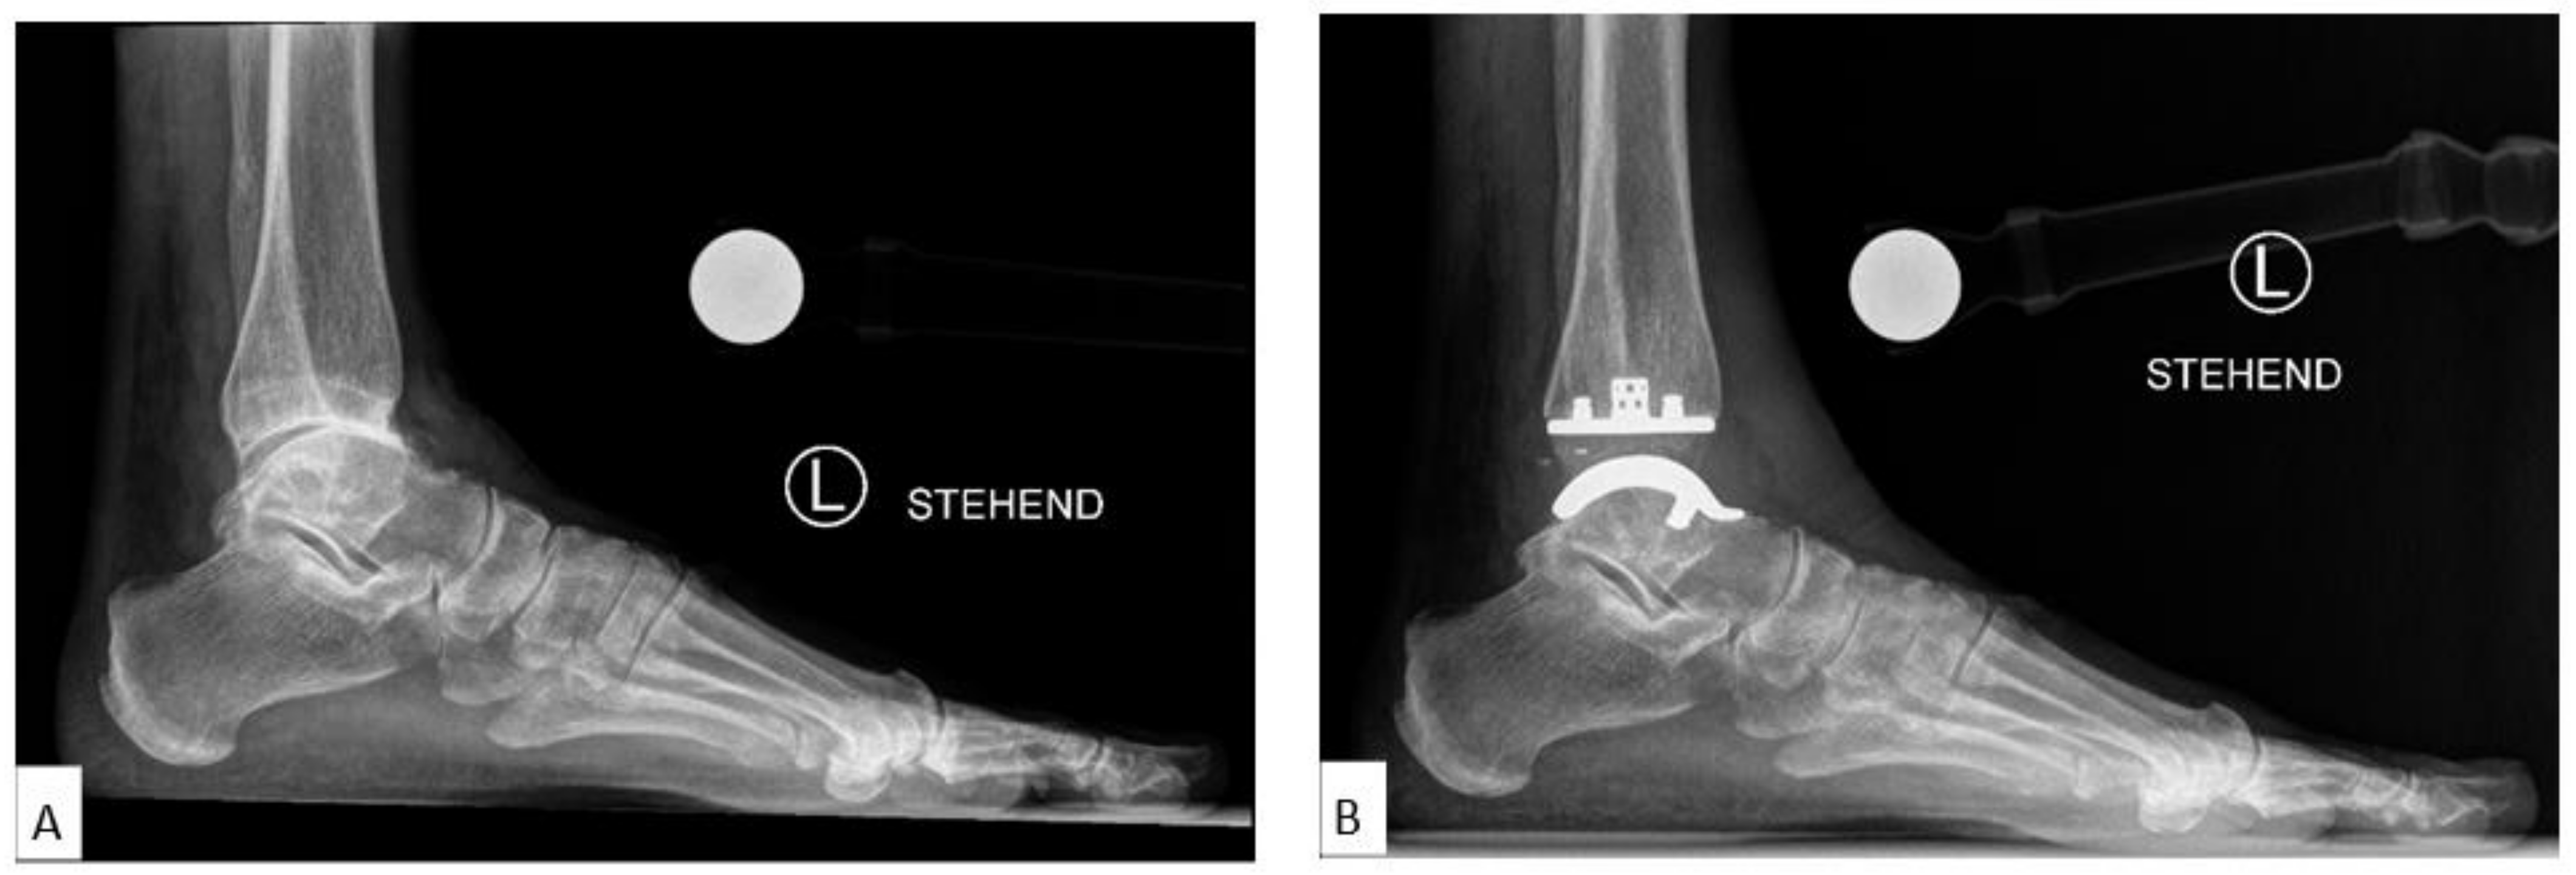

The medial distal tibial articular angle (mDTAA, degrees) [18] on the ankle OA as well as on the TAA as medial tibial component coronal angle were used to identify coronal alignment, measured on the anteroposterior radiograph as the medial angle subtended by the anatomic axis of the tibia and the tibial plafond line or inferior border of the tibial component, with positive values equal to valgus result and negative values equal to varus result (Figure 2A,B). The sagittal alignment assessed was by the anterior distal tibial articular angle (aDTAA, degrees) [19] on the ankle OA and on the TAA as anterior tibial baseplate angle [14,20] on the lateral radiograph, measured as the anterior angle formed from the anatomic axis of the tibia and the line connecting the distal points on the anterior and posterior tibial articular surface or inferior border of the tibial component (Figure 2C,D).

Figure 2.

Preoperative and Postoperative Radiological Measurements. (A): Medial distal tibial articular angle (mDTAA) on the ankle osteoarthritis (OA), (B): Medial distal tibial articular angle (mDTAA) on the total ankle arthroplasty (TAA) as medial tibial component coronal angle, (C): Anterior distal tibial articular angle (aDTAA) on the ankle OA, (D): Anterior distal tibial articular angle (aDTAA) on the TAA as anterior tibial baseplate angle. Lateral talar station (LTS). (E): Preoperative on the ankle OA, (F): Postoperative on the TAA.

Among the methods listed above, we utilised the LTS (Lateral Talar Station, mm) technique described in the literature as the most reproducible and least sensitive to sagittal ankle position, with defined normal ranges, to quantify sagittal talar position. The LTS method as described by Veljkovic et al. [16]—a modification of the previously described TibCOR measurement by Magerkurth et al. [12]—measures the distance between the tibial long axis, defined as a line joining the centre of two circles in the tibia (10 cm and 5 cm from tibial plafond), and a perpendicular line extending to the centre of rotation of the talus (as an average of the two condylar centres of rotation), reported in millimetres. Values were defined as high if the centre of the circle was anterior to the tibial axis (>3.1496 mm) and low if lying posterior to the tibial axis (<−0.8076 mm) [16] (Figure 2E,F). In order to get more insight into the LTS measurement, the following subgroups analyses were performed: LTS (overall total values), LTS-A: preoperatively anteriorly subluxated ankle OA cases, LTS-P: preoperatively posteriorly subluxated ankle OA cases, LTS-N: preoperatively non-subluxated ankle OA cases.

The mean LTS (Lateral Talar Station, mm) values for all patients were 3.95 mm ± SE 0.78 (range: −11.52 to 13.89) preoperatively and 1.14 mm ± SE 0.63 (range: −10.76 to 11.75) at 12 months, with a statistically significant difference between preoperative and 12-month follow-up (p = 0.01). The mean LTS for 27 TAA with anterior subluxation (LTS-A) preoperatively was 7.99 mm ± SE 0.54 (range: 3.30–13.89) and 1.59 mm ± SE 0.71 (range: −5.72 to 11.75) at 12 months postoperatively, with a highly statistically significant difference between preoperative and 12-month values (p < 0.00001). The mean LTS for 16 TAA with no subluxation (LTS-N) preoperatively was 1.22 ± SD 1.02 (range: −0.63 to 2.70) and 2.01 ± SD 4.82 (range: −10.67 to 10.48) at 12 months postoperatively, with no statistically significant difference between preoperative and 12-month values (p = 0.53). The mean LTS for 7 TAA with posterior subluxation (LTS-P) preoperatively was −5.44 ± SD 3.63 (range: −11.52 to −2.17) and −2.55 ± SD 5.13 (range: −10.76 to 3.20) at 12 months postoperatively with, no statistically significant difference between preoperative and 12-month values (p = 0.25) (Table 3) (Figure 3A,B).

Figure 3.

Case with Centralization of Talus after Implantation of VANTAGE Mobile Bearing Total Ankle Arthroplasty. The talar centre of rotation/Lateral Talar Station (LTS) converged toward the longitudinal tibial axis from 10 mm preoperatively (A) to 2 mm postoperatively in 12 months follow-up radiograph (B).